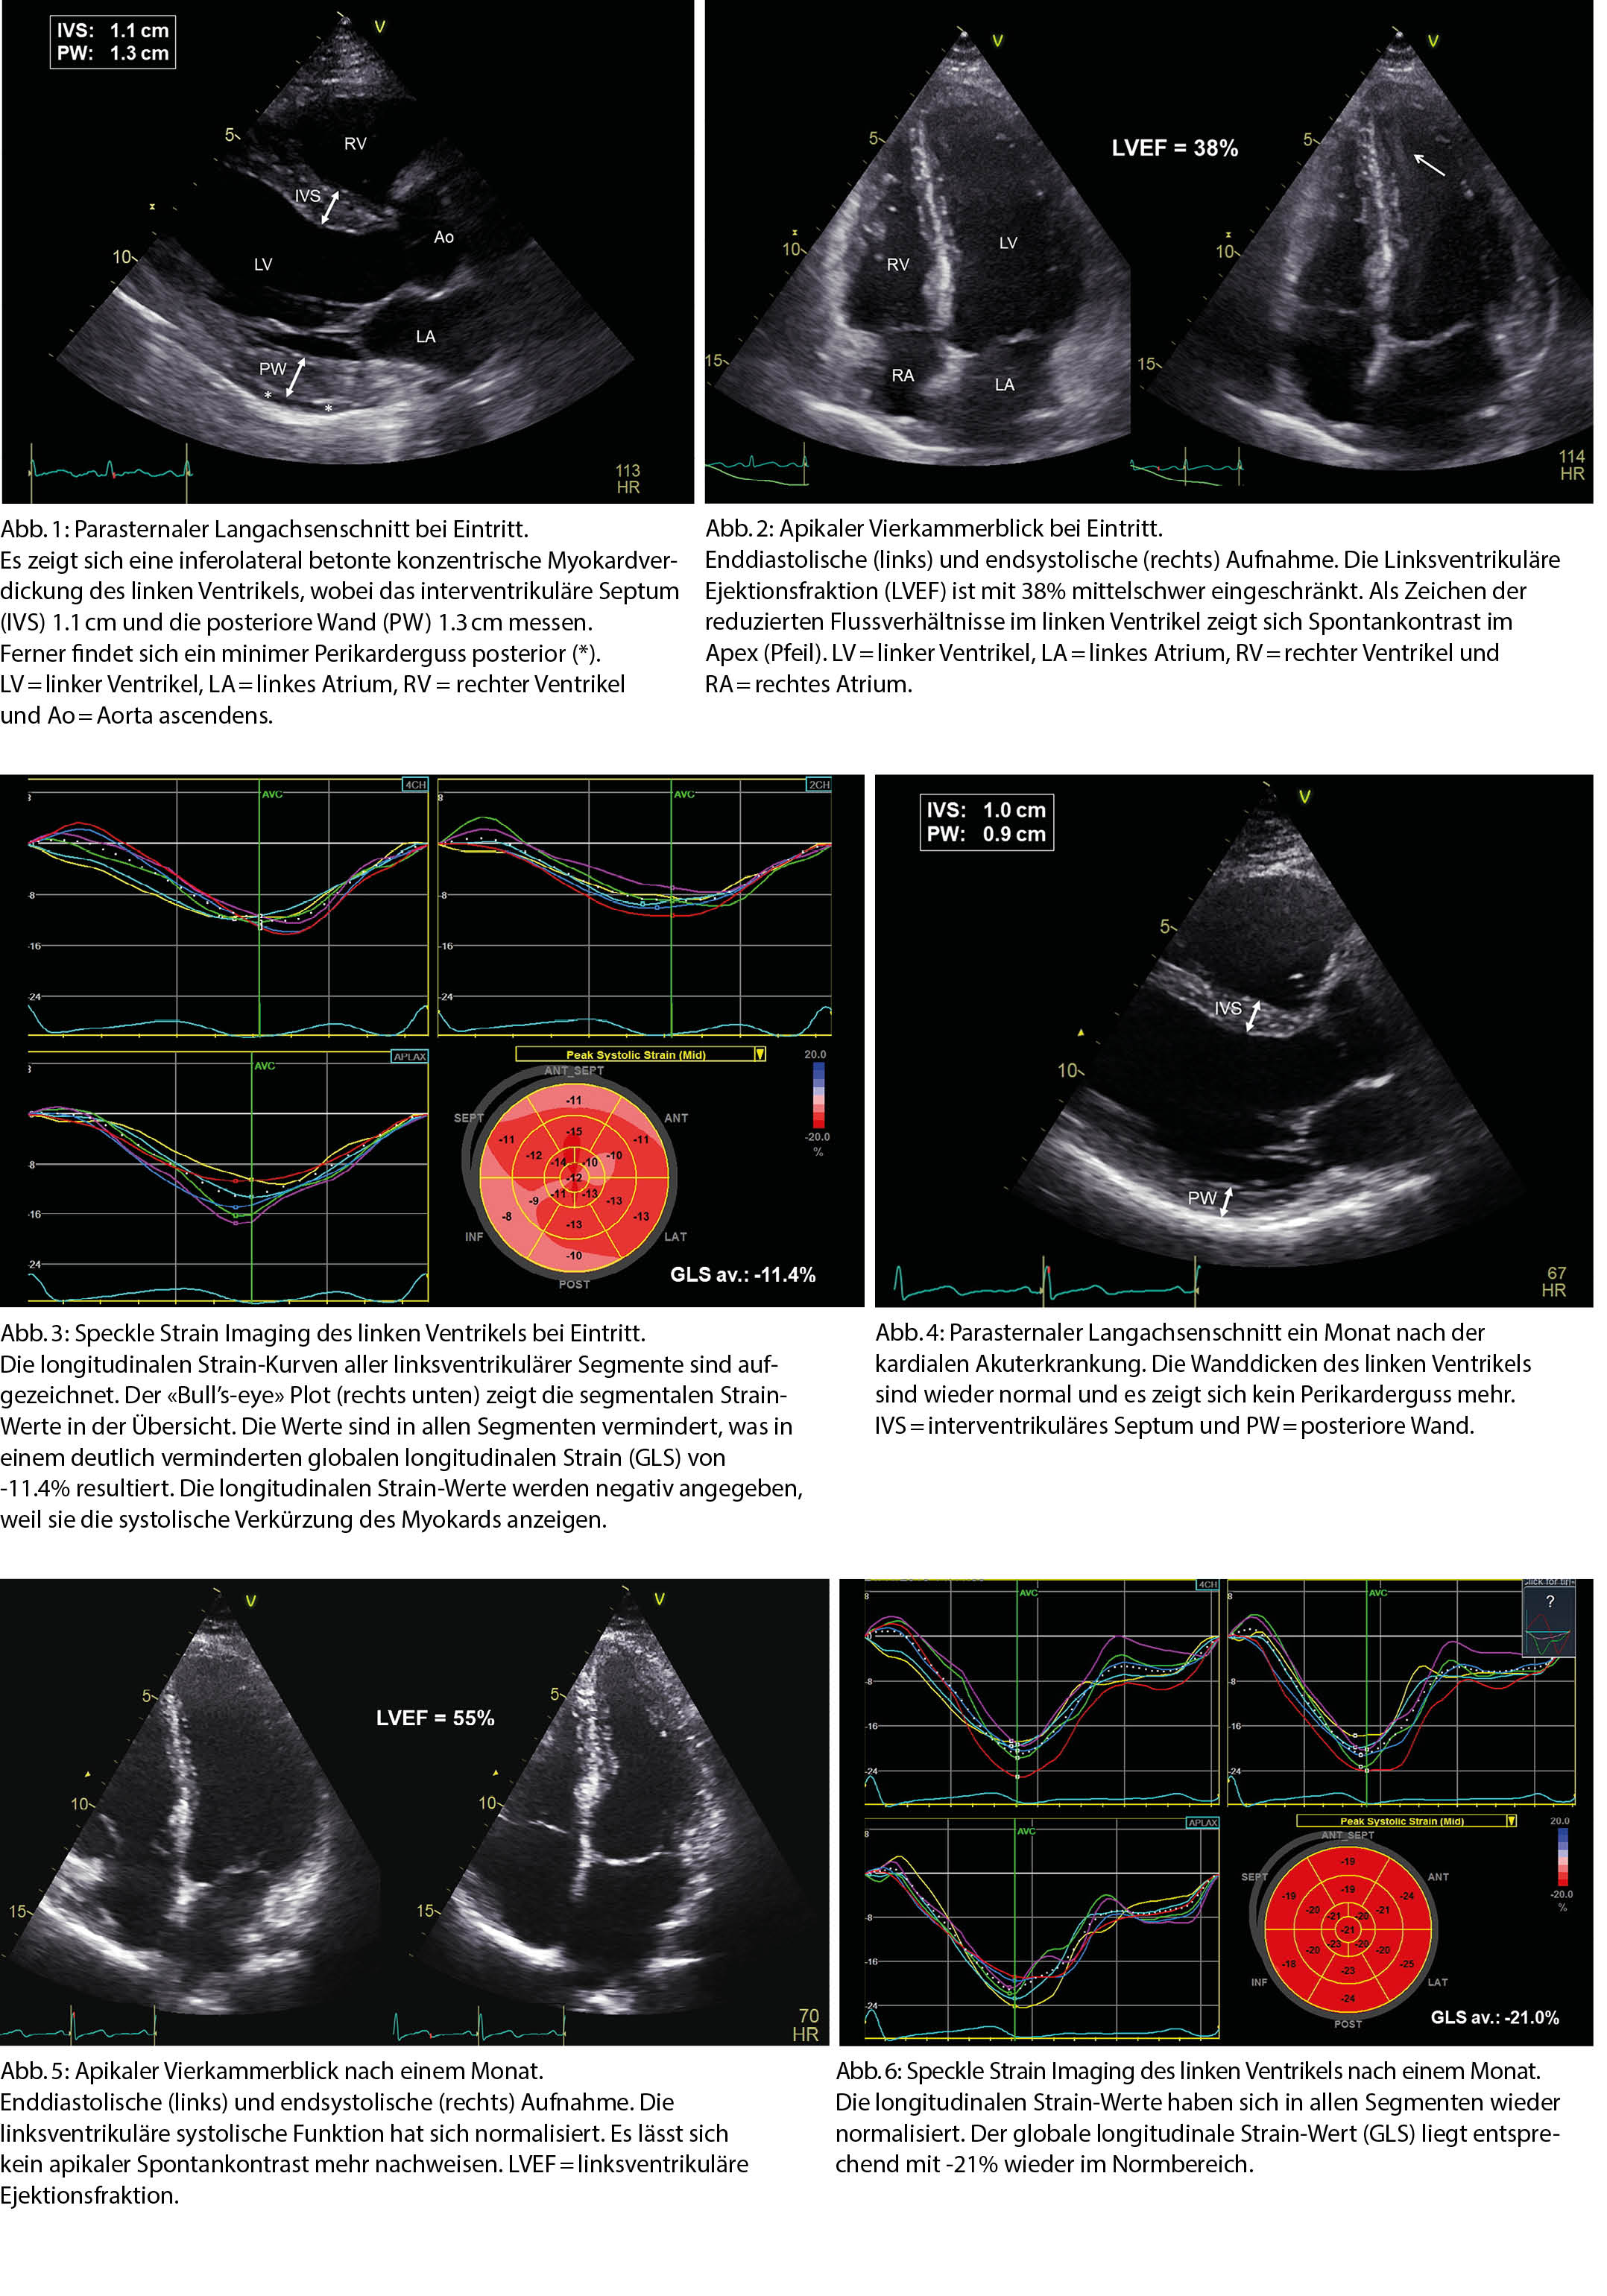

Eine 33-jährige Patientin musste wegen einer schweren paranoiden Schizophrenie in einer psychiatrischen Klinik hospitalisiert werden. Es erfolgte eine medikamentöse Einstellung mit Clozapin und Amisulprid. Im Laufe der Hospitalisation klagte die Patientin über zunehmende Müdigkeit, Kopfschmerzen, Gliederschmerzen und trockenen Reizhusten. In der Folge kam es auch zu zunehmender Dyspnoe, so dass die Patientin notfallmässig ins Akutspital verlegt werden musste. Bei Eintritt war die Patientin subfebril und tachykard mit einer Herzfrequenz von 120 pro Minute. Der Blutdruck lag bei 100/50mmHg. In der klinischen Untersuchung fanden sich keine eindeutigen Stauungszeichen. Radiologisch zeigte sich eine knapp kompensierte Lungenzirkulation. Das EKG zeigte keine spezifischen Veränderungen. Im Labor fielen eine deutliche Leukozytose, ein CRP von 287 mg/l (Norm < 10) und ein hochsensitives (hs) Troponin T von 245 pg/l (Norm < 14) auf. Als zusätzliche Untersuchung wurde eine transthorakale Echokardio-graphie durchgeführt. Hierbei zeigte sich eine konzentrische linksventrikuläre (LV) Myokardverdickung, welche inferolateral betont war. Ferner fand sich ein minimer Perikarderguss (Abb. 1). Die LV Ejektionsfraktion (EF) war mit 38% mittelschwer eingeschränkt und es zeigte sich Spontankontrast im LV Apex (Abb. 2). Der globale longitudinale Strain (GLS) war mit -11.4% deutlich eingeschränkt (Abb. 3), was auf eine erhebliche Einschränkung der myokardialen Longitudinalfunktion hinwies. Aufgrund der erhobenen Befunde ergab sich das Bild einer akuten Myokarditis. An welche Ursache hierfür muss bei dieser Patientin im Besonderen gedacht werden?

Differentialdiagnostisch war einerseits eine infektiöse Genese der akuten Myokarditis denkbar. Daneben musste jedoch auch an eine Nebenwirkung von Clozapin, welches kurze Zeit vor der akuten kardialen Erkrankung initialisiert wurde, gedacht werden. Bei möglicher Clozapin-induzierter Myokarditis wurde dieses Medikament umgehend gestoppt und eine medikamentöse Herzinsuffizienztherapie eingeleitet. Fünf Tage nach Sistierung von Clozapin zeigte sich ein Rückgang des CRP auf 123 mg/l und des hs Troponins T auf 39 pg/l. Dies ging sowohl mit einer Verbesserung der LVEF auf 45%, als auch mit einer klinischen Verbesserung einher. Einen Monat später zeigte die Kontrollechokardiographie bei kardial nunmehr beschwerdefreier Patientin eine Normalisierung der Dimensionen des LV Myokards (Abb. 4), welches retrospektiv anfangs durch den entzündlichen Prozess mit konsekutivem intramyokardialem Ödem verdickt war. Ferner fanden sich eine Normalisierung der LVEF auf 55% (Abb. 5) und des GLS auf -21% (Abb. 6).